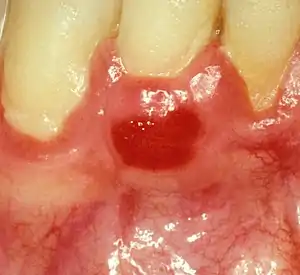

| Plasma cell gingivitis in an adult (histologically verified). | |

Plasma cell gingivitis appears as mild gingival enlargement and may extend from the free marginal gingiva on to the attached gingiva.[6] Sometimes it is blended with a marginal, plaque induced gingivitis, or it does not involve the free marginal gingiva. It may also be found as a solitude red area within the attached gingiva (pictures). In some cases the healing of a plaque-induced gingivitis or a periodontitis resolves a plasma cell gingivitis situated a few mm from the earlier plaque-infected marginal gingiva. In case of one or few solitary areas of plasma cell gingivitis, no symptoms are reported from the patient. Most often solitary entities are therefore found by the dentist.[2]

The gums are red, friable, or sometimes granular, and sometimes bleed easily if traumatised.[6] The normal stippling is lost.[7] There is not usually any loss of periodontal attachment.[6] In a few cases a sore mouth can develop, and if so pain is sometimes made worse by toothpastes, or hot or spicy food.[7] The lesions can extend to involve the palate.[7]